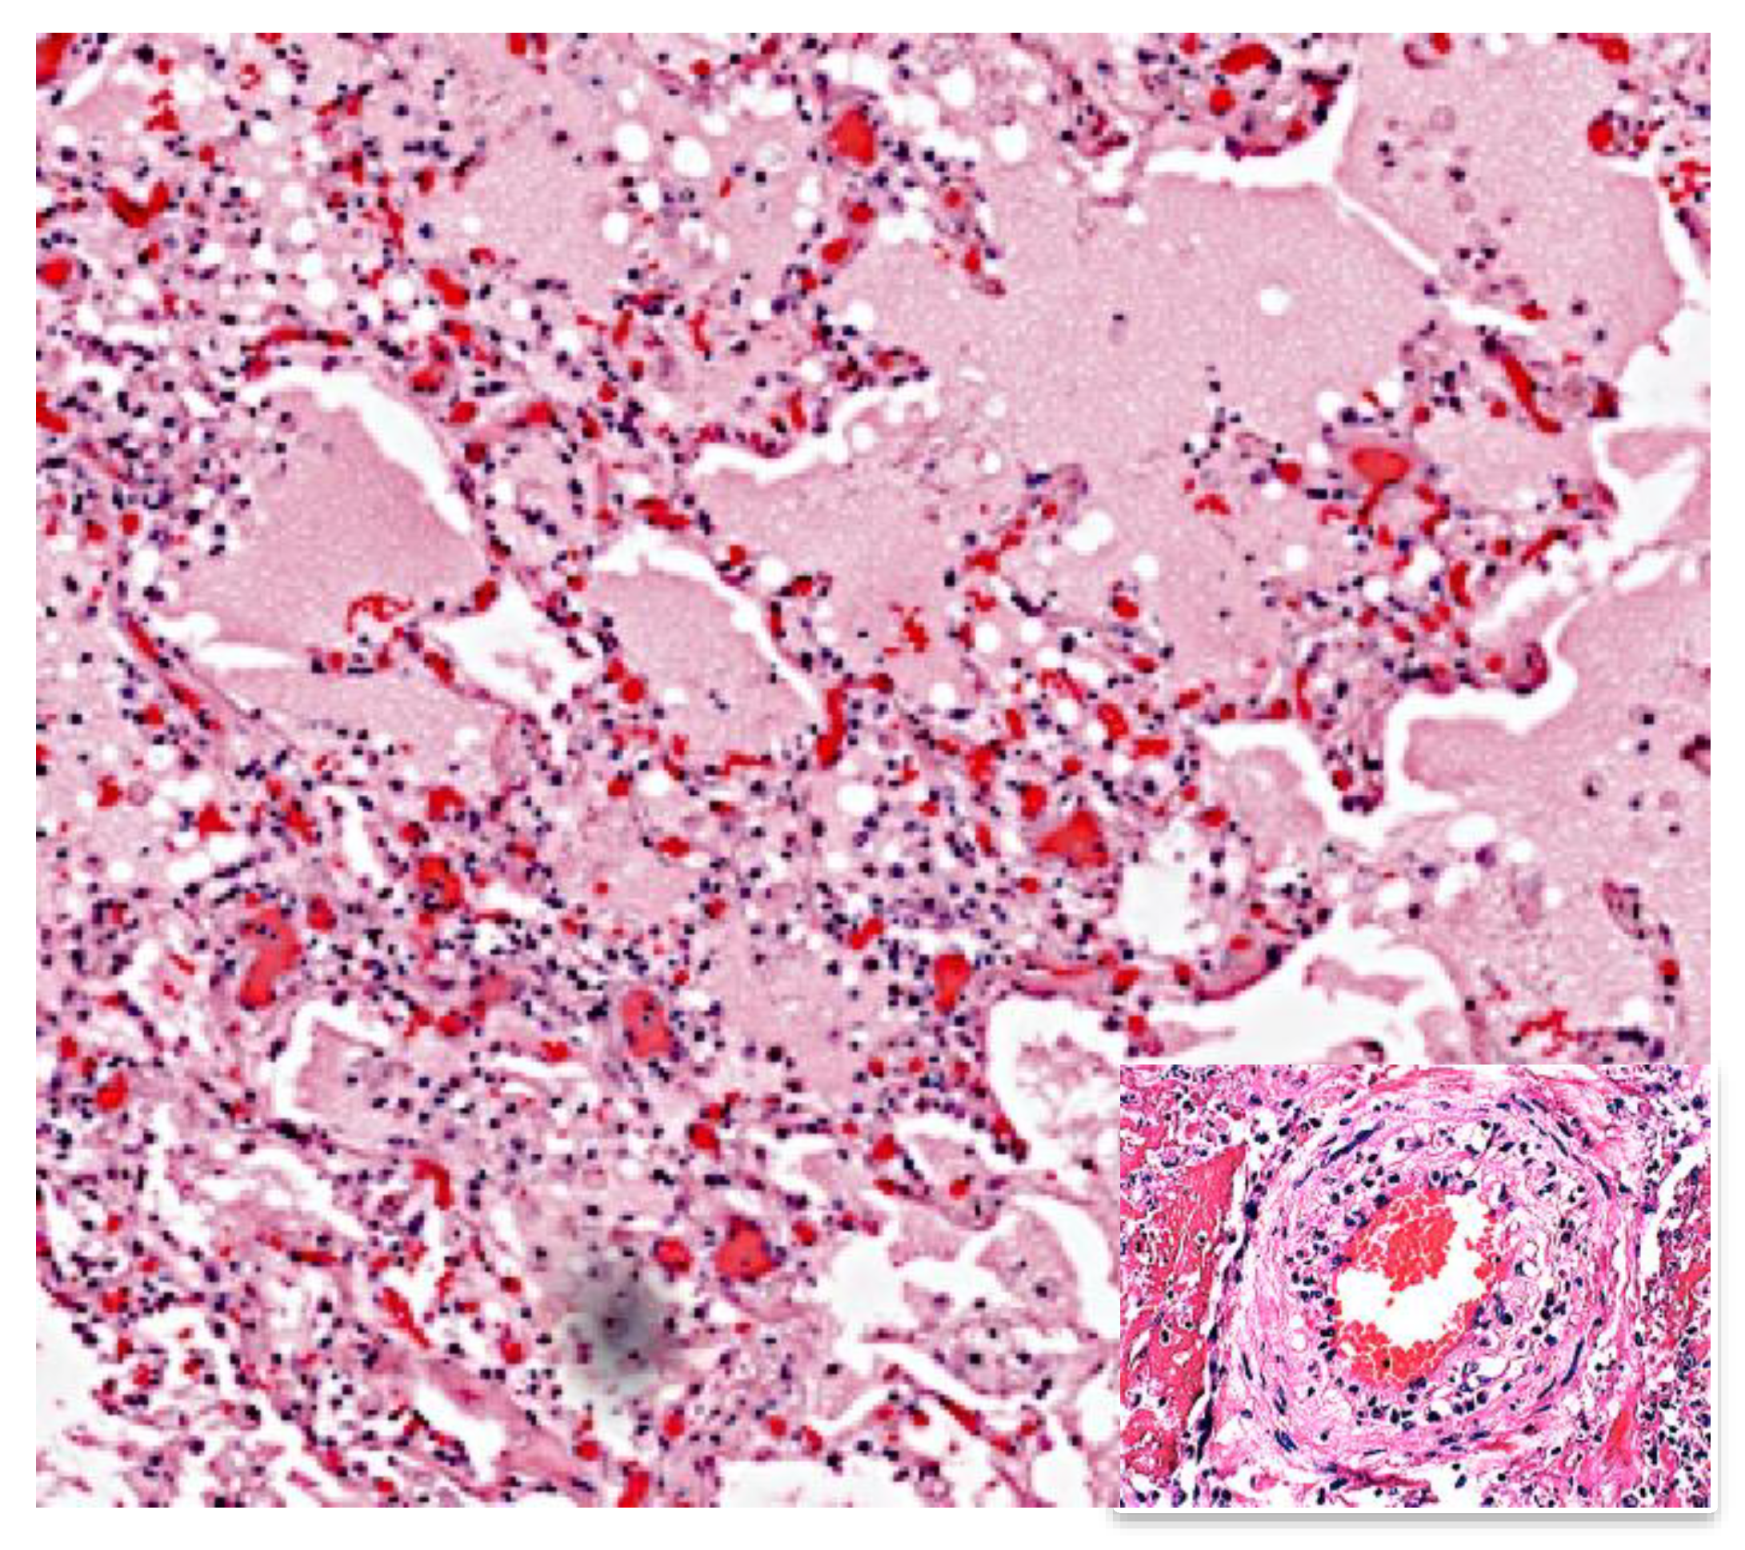

- Pagel, W. Zur Histochemie der Lungentuberkulose, mit besonderer Berucksichtung der Fettsubstanzen und Lipoide. (Fat and lipoid content to tuberculous tissue. Histochemical investigation.). Virchows. Arch. Pathol. Anat. 1925, 256, 629–640. [Google Scholar] [CrossRef]

- Birkun, A.A. Disorders of fat metabolism in the lungs in tuberculosis. (pathomorphological and histochemical characteristics). Arkhiv. Patol. 1963, 25, 23–32. [Google Scholar]

- Russell, D.G.; Cardona, P.J.; Kim, M.J.; Allain, S.; Altare, F. Foamy macrophages and the progression of the human tuberculosis granuloma. Nat. Immunol. 2009, 10, 943–948. [Google Scholar] [CrossRef] [PubMed]

- Hunter, R.L.; Olsen, M.; Jagannath, C.; Actor, J.K. Trehalose 6,6′-dimycolate and lipid in the pathogenesis of caseating granulomas of tuberculosis in mice. Am. J. Pathol. 2006, 168, 1249–1261. [Google Scholar] [CrossRef]

- Riaz, S.M.; Bjune, G.A.; Wiker, H.G.; Sviland, L.; Mustafa, T. Mycobacterial antigens accumulation in foamy macrophages in murine pulmonary tuberculosis lesions: Association with necrosis and making of cavities. Scand. J. Immunol. 2020, 91, e12866. [Google Scholar] [CrossRef]